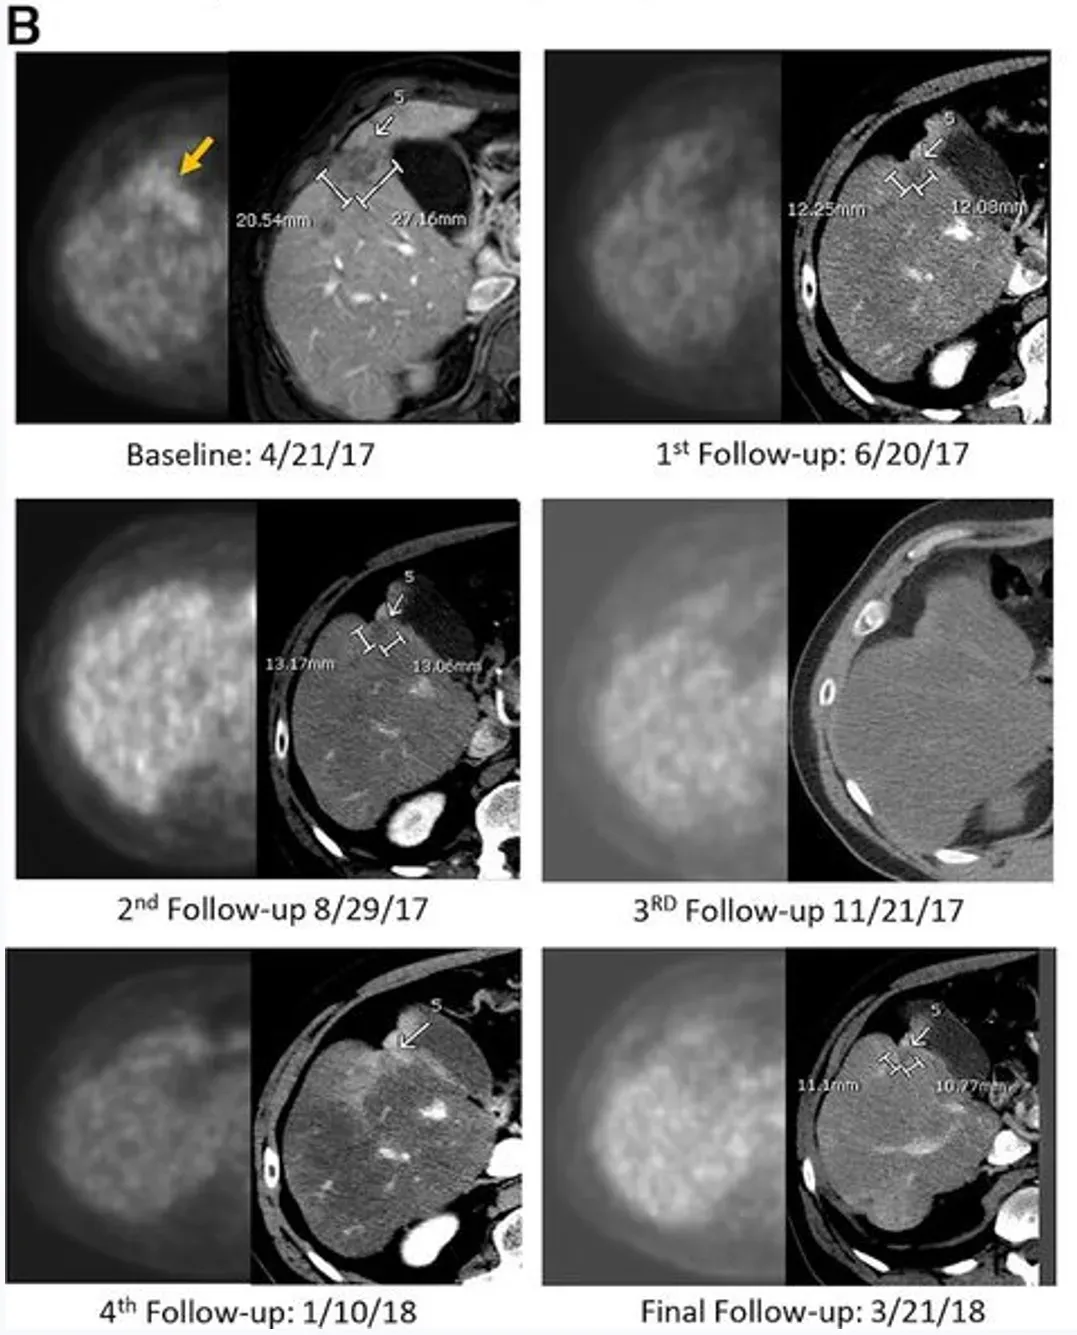

下图展示了一例59岁男性Kras突变型直肠癌患者的影像对比图:该患者既往接受过3线治疗,在接受IM96 CAR-T治疗后,其肺部、肝部的转移病灶均显著缩小。

治疗结果显著:CAR-T输注6周后,正电子发射断层扫描(PET-CT)显示肝脏内原氟脱氧葡萄糖(FDG)阳性病灶完全无代谢活性,该完全代谢反应持续13个月;静脉增强CT提示目标病灶稳定或略缩小,无新增转移灶。治疗3.7个月时,PET扫描显示肝脏仍维持无代谢活性,但胰头原发灶代谢活性升高,患者随即接受以5-氟尿嘧啶为放射增敏剂的胰腺肿块放疗,后续扫描显示原发肿瘤灶亦达到完全代谢缓解。

从生存期来看,该患者总生存期(OS)长达23.2个月——而多数IV期胰腺腺癌患者中位生存期仅5个月,意味着CEA CAR-T疗法让这位化疗耐药患者的生存期延长了近5倍(4.64倍)。

肿瘤标志物层面,以治疗中最低点计算,患者CEA下降81%、糖类抗原19-9(CA19-9)下降68%,且两类标志物均在治疗后2-3个月内恢复正常。病理分析进一步显示,肝肿瘤活检标本出现大面积透明纤维化,无正常肝组织损伤迹象,且标本中检测到大量CAR+细胞。